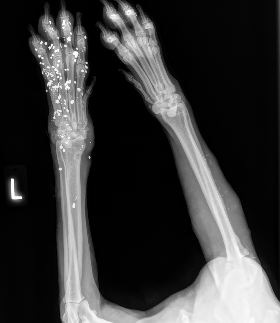

Squid came to us from a partner shelter that was unable to provide the care he needed after being shot in the leg with birdshot. X-rays revealed multiple pellets lodged in his leg, causing significant pain and putting him at risk for complications, including lead toxicity if left untreated.

Our veterinary team is evaluating the extent of his injuries, and he will likely require an amputation to relieve his pain and give him the best chance at a healthy life. ?